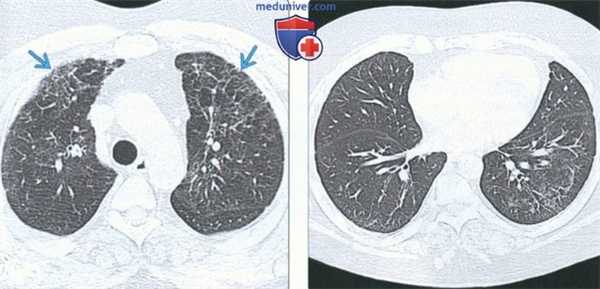

(Слева) На аксиальной КТВР у пациента с перибронхиальным интерстициальным фиброзом определяется утолщение перибронхиальных тканей наряду с деформацией бронховаскулярных пучков и «мозаичной» картиной легочной ткани.

(Справа) На аксиальной экспираторной КТВР у этого же пациента определяется «географическая» или «мозаичная» картина, обусловленная заболеванием периферических дыхательных путей. Обратите внимание на небольшой диаметр легочных сосудов в участках со сниженной плотностью. Наиболее типичными причинами перибронхиального интерстициального фиброза являются гиперчувствительный пневмонит и гастроэзофагеальная рефлюксная болезнь. (Слева) На аксиальной КТВР у пациента с перибронхиальным интерстициальным фиброзом определяется утолщение перибронховаскулярных тканей на фоне тракционных бронхоэктазов и слабо выраженной «мозаичной» картины. Обратите внимание на воздушные «ловушки» в пределах легочных долек.